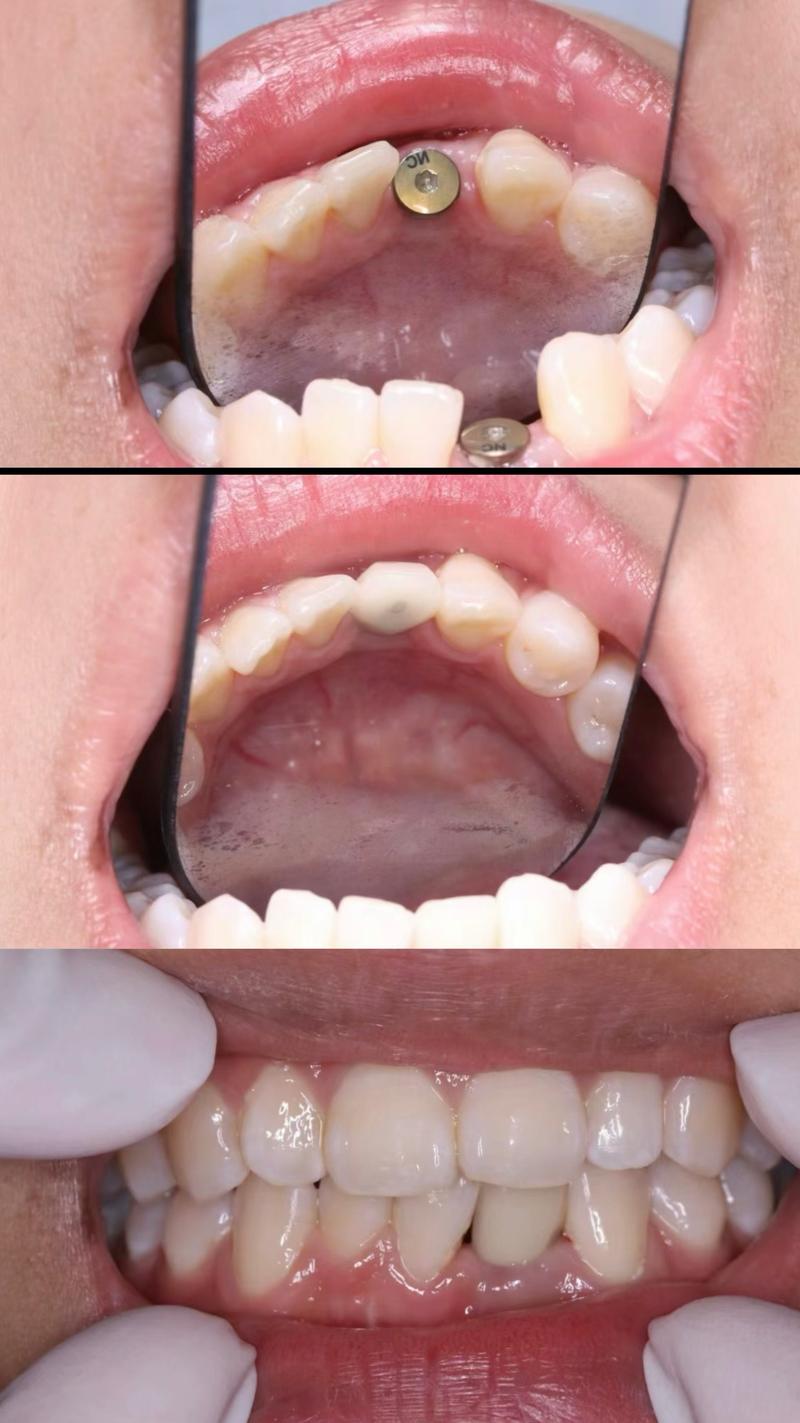

植得口腔的矫正案例库覆盖儿童、青少年及成人各类错颌畸形,从简单的牙列拥挤到复杂的骨性开颌,均取得了良好效果,12岁的患儿因“牙列拥挤伴上颌前突”,通过早期干预(扩弓+前方牵引),引导颌骨正常发育,避免了成年后正颌手术;35岁成人患者因“牙齿稀疏伴中线偏斜”,采用隐形矫正关闭间隙,调整中线,同时改善“凸嘴”问题,侧貌轮廓更柔和;45岁患者因“牙周病导致的牙齿移位”,通过正畸联合牙周治疗,排齐牙齿的同时稳定牙周组织,恢复了正常咀嚼功能,这些案例不仅体现了植得口腔的技术实力,更彰显了其“功能与美学并重”的矫正理念。